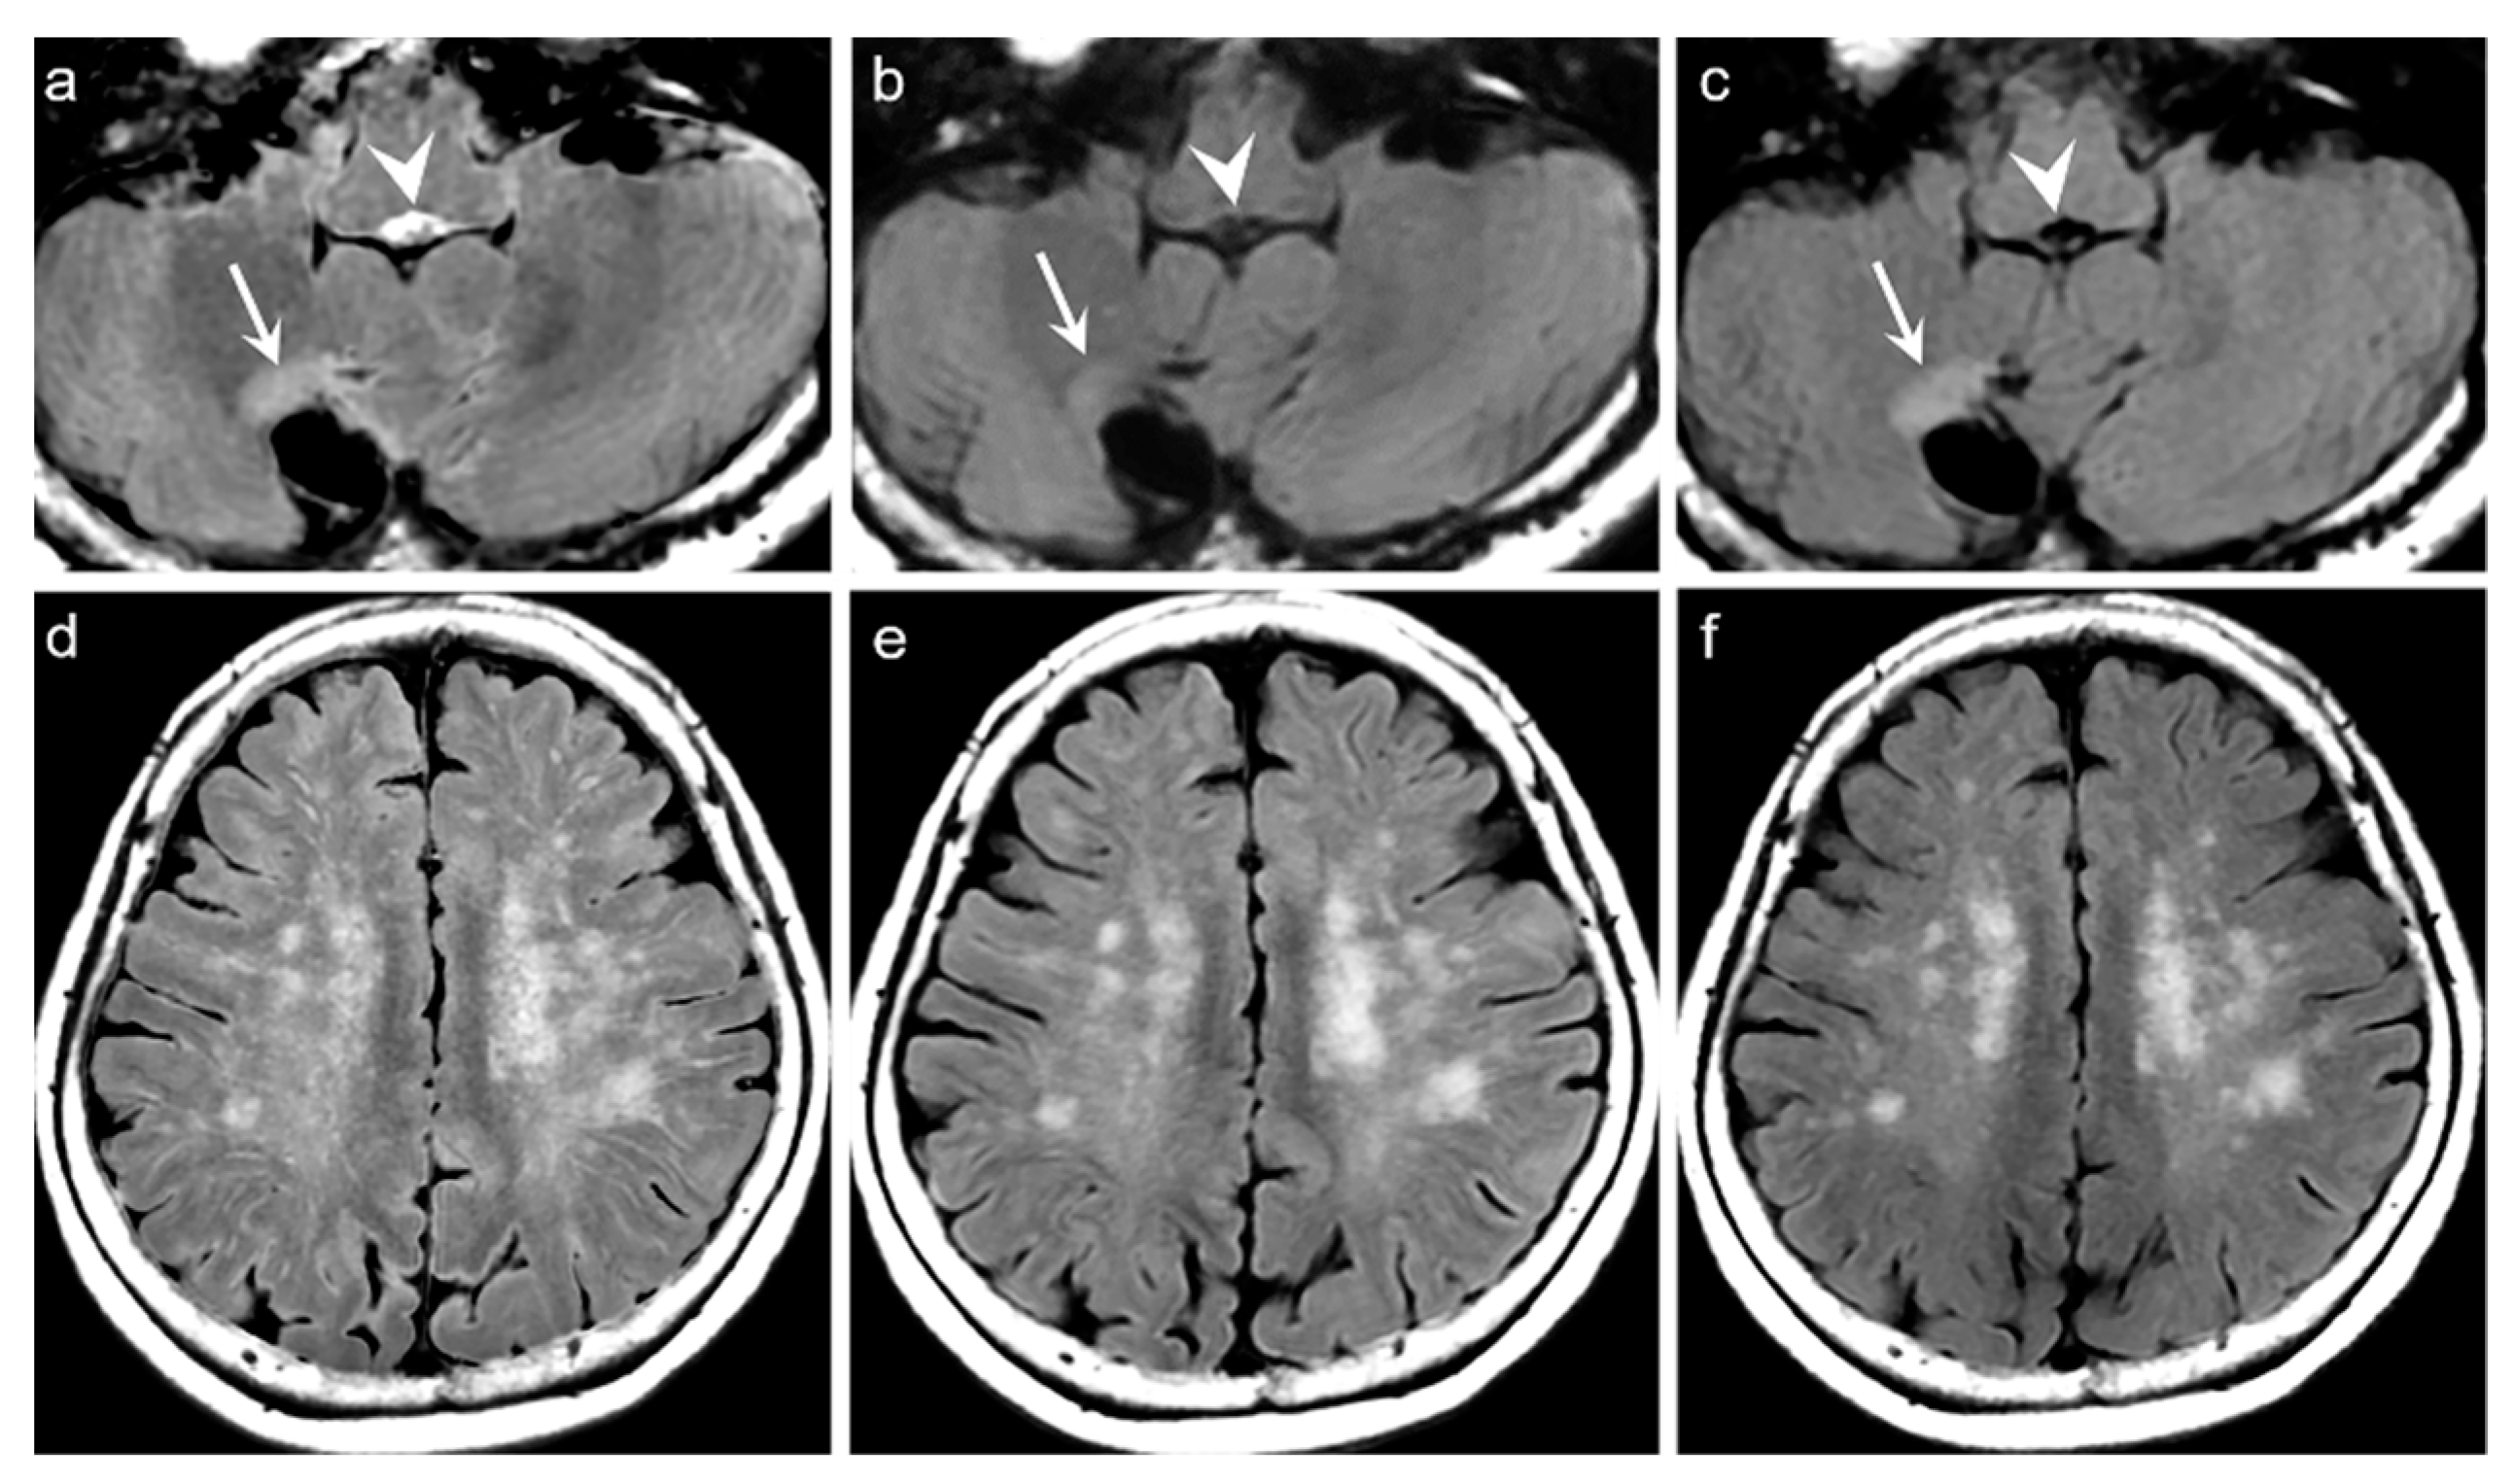

p < 0.0001). The average mean scores of the degree of preserving the preexisting periventricular WM hyperintensities or lesion conspicuity were not statistically significant for DL-FLAIR and native synthetic FLAIR: 4.69 ± 0.68 vs. 4.70 ± 0.61 (

p = 0.217). Among the 319 patients, there was no case of generation of artificial pseudolesions during DL processing. However, it was possible to identify incomplete preservation of the preexisting true hyperintensities on DL-FLAIR images in 11 patients (3.4%) among 319 patients owing to the unexpected partial removal of the true hyperintensities (

Figure 3b and

Figure 4b). The mean scores of the typical synthetic FLAIR artifacts including surface hyperintensities, granularities, or cortical swelling were identified for DL-FLAIR and native synthetic FLAIR images as follows: 1.32 ± 0.51 vs. 3.35 ± 0.68 (

In the present study, we could identify the incomplete preservation of pre-existing true hyperintensities on DL-FLAIR images in 11 patients, owing to the unexpected partial removal of the true hyperintensities. In all these cases, the hyperintense lesions were located in the vicinity of cystic encephalomalacias, and the lesions were considered to be reactive gliosis. The reason for this finding is unclear; however, it may be related to the processing of DL-based artifact correction to distinguish artifacts from true hyperintensities, especially when the true hyperintensities were seen near fluid-containing lesions, making the fluid-lesion interface likely to be similar to the CSF-brain parenchyma interface. We believe that the issue can be solved if the DL algorithm is improved through a further training process using various pathologic cases that can differentiate a normal CSF-tissue interface from the lesion-fluid interface.